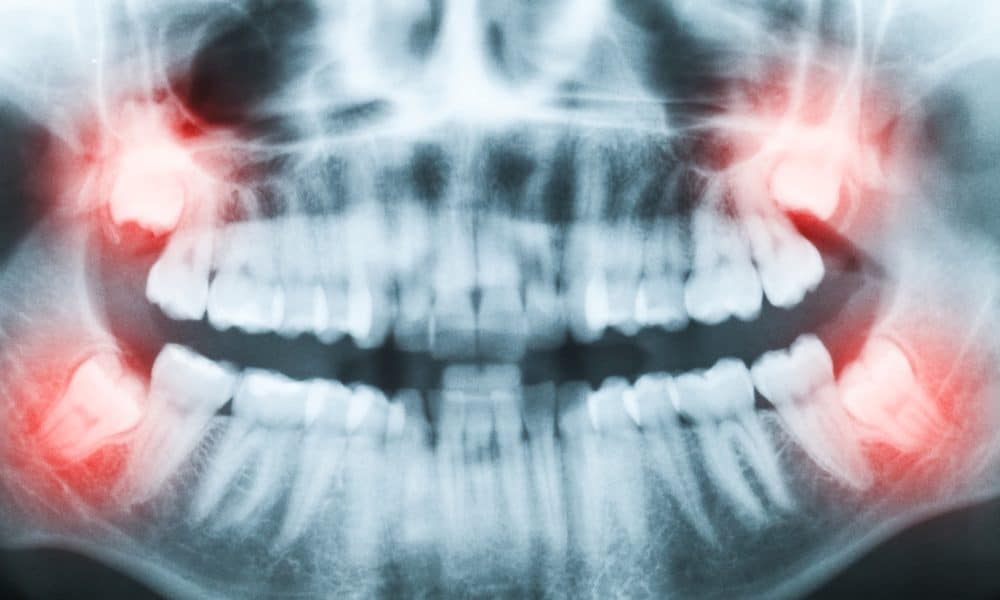

What to Expect at Your Consultation

A consultation helps us determine whether you will benefit from wisdom tooth removal and what type of surgical removal is appropriate. We will review your health care background, take the appropriate x-rays, and evaluate how your third molars relate to surrounding bone, gum tissue, and nearby teeth.

During your visit, we will discuss:

• The position of your wisdom teeth and whether they are impacted.

• Whether there is enough room for proper eruption and cleaning.

• The difficulty of the wisdom tooth extraction.

• Your type of anesthesia options, including local anesthesia and general anesthesia when appropriate.

• A clear plan for oral surgery, recovery, and follow-up.